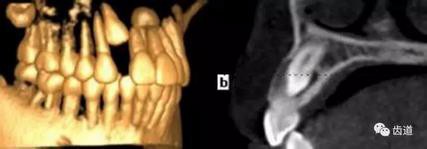

1、上頜尖牙阻生

上頜尖牙埋伏阻生在CBCT中的影像

3、顳下頜關(guān)節(jié)

顳下頜關(guān)節(jié)CBCT影像